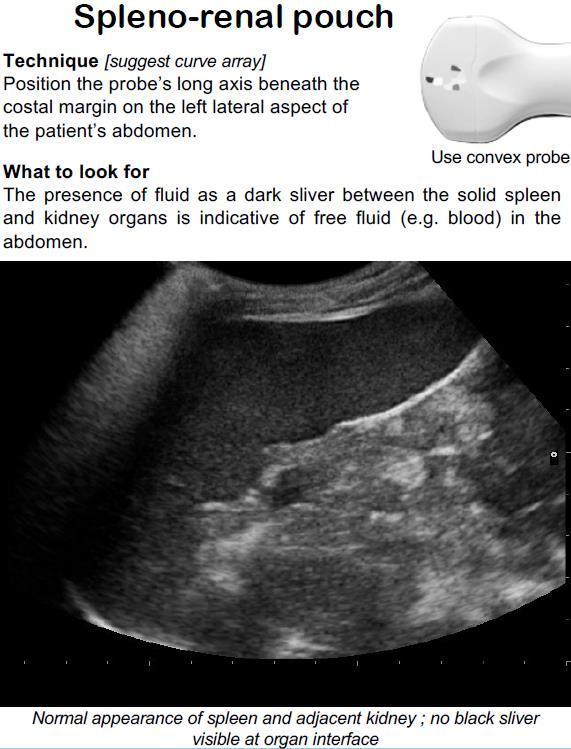

This week, Aebhric talks with Dr. Slaven Bajic, who teaches our Austere and Prehospital Ultrasound course. He is from Slovenia, where he runs the A&E department at his local hospital.